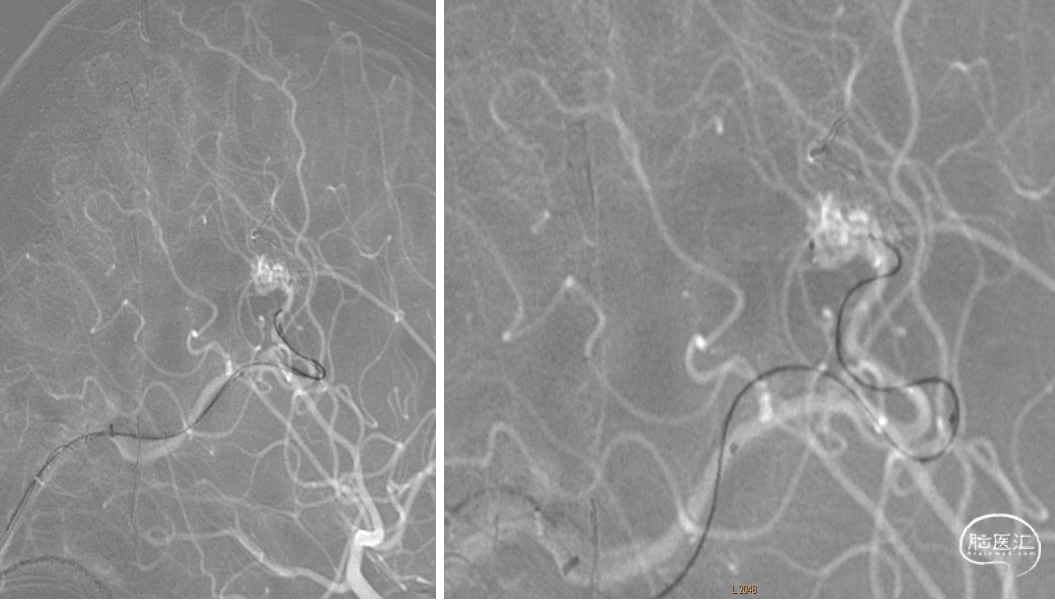

DSA:右侧额顶叶脑动静脉畸形

15%外科胶做塞子,注射Onyx18栓塞